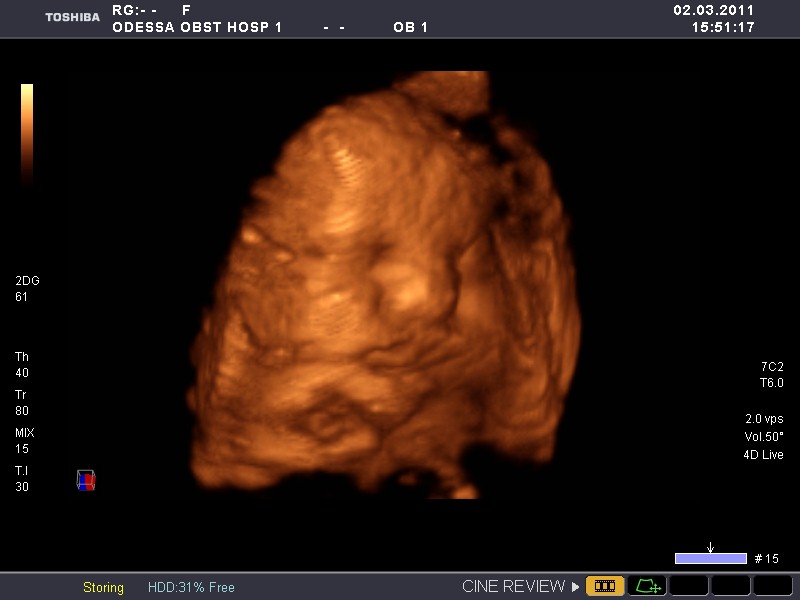

А это фото с УЗИ в 32 нед. Похож?

Вложение 2684654Вложение 2684655

Ух красавцы!!!!! ттт... Поздравляю!!!!!!!!!!!!!!!!! А масик и правда оч похож!

ооо...ПО3дравляю ВАС!!Вас жорик младше нашего мирошки ровно на три дня)Но вы такие уже крупнячки!!!ТТТ на вас!Растите 3доровенькими))